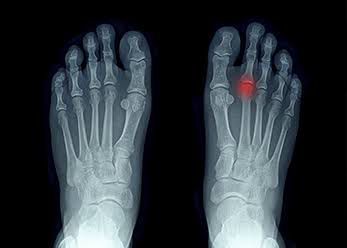

Common signs and symptoms include pain and stiffness in the front of the foot, which often leads to a limp. Affected people may also experience swelling, limited range of motion, and tenderness of the affected foot. Symptoms are generally triggered by weight-bearing activities, including walking.